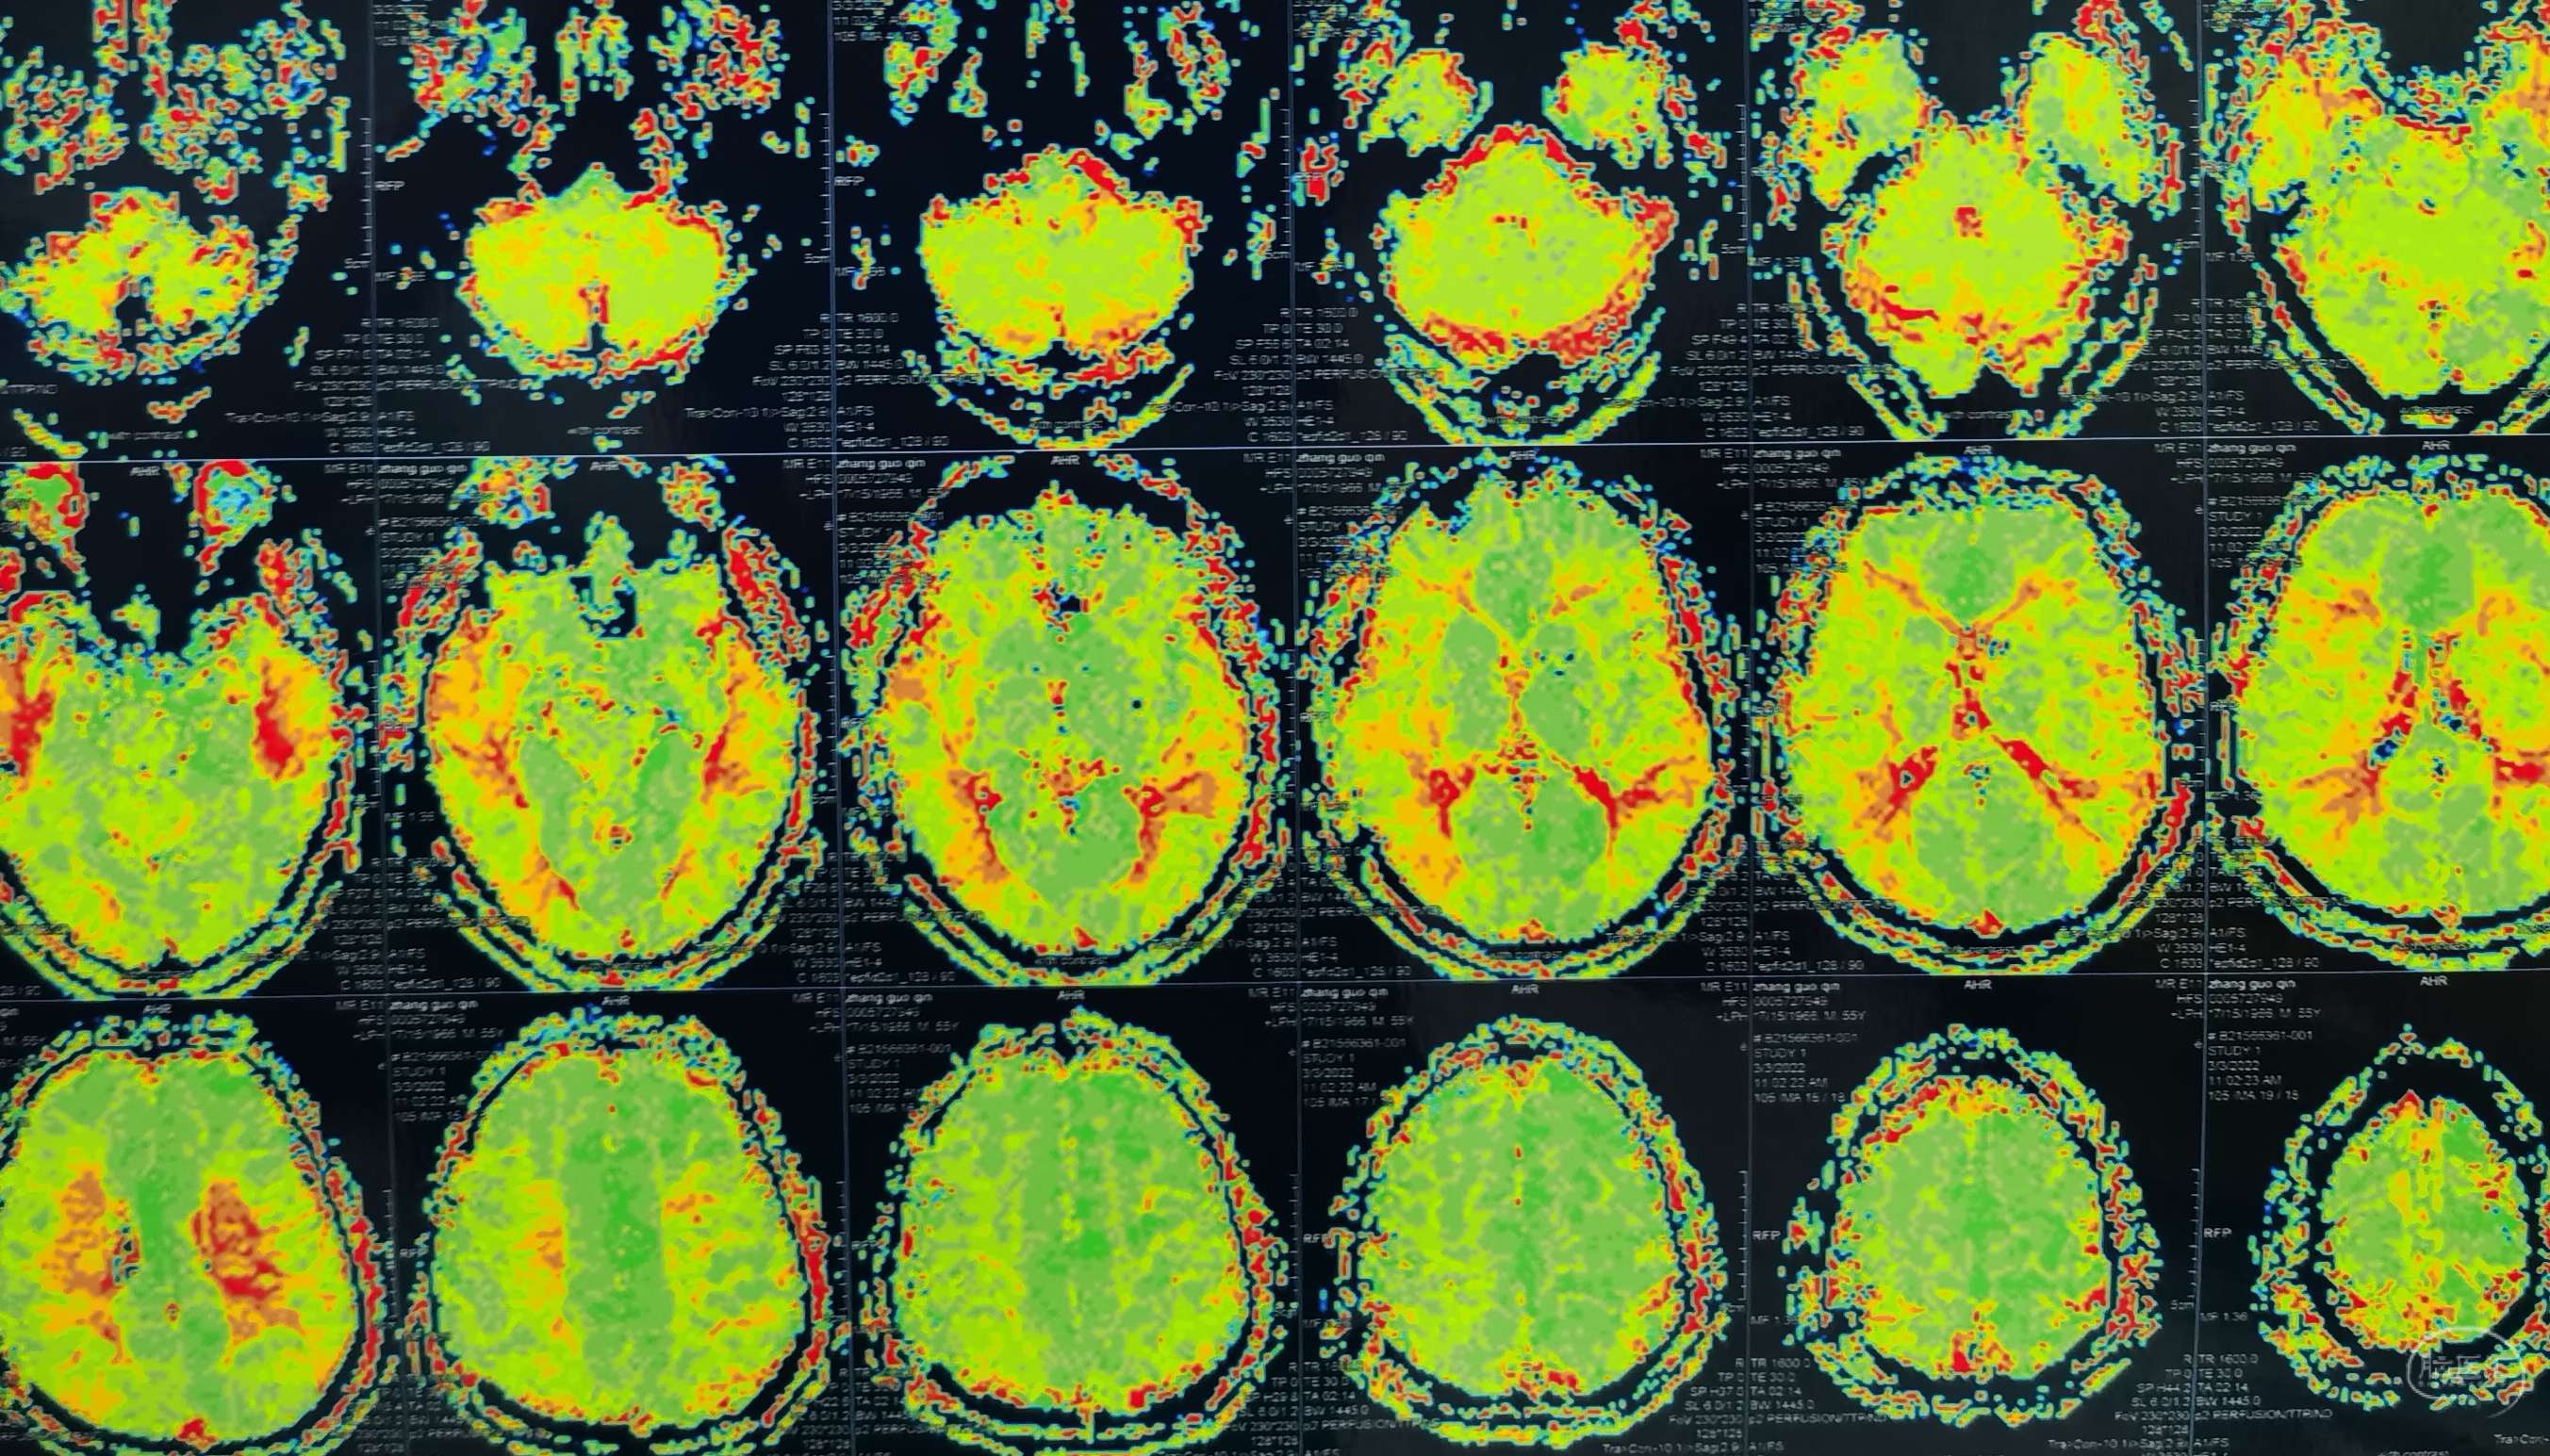

脑灌注提示:左侧大脑半球低灌注缺血。

脑灌注提示:右侧大脑半球低灌注缺血。

脑灌注提示:双侧大脑半球低灌注缺血。

脑灌注提示:双侧大脑半球低灌注缺血。

脑灌注提示:双侧大脑半球低灌注缺血。